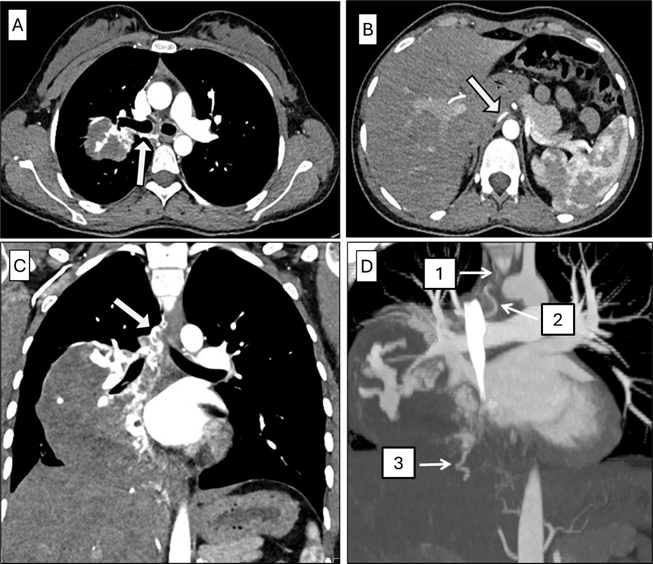

Incidental Finding of a Retroaortic Left Renal Vein with Pelvic Venous Congestion Consistent with Posterior Nutcracker Syndrome: A Case Report

Antonia Berz, Théo Sartoretti, Rami Hajri, Guillaume Fahrni

1-10